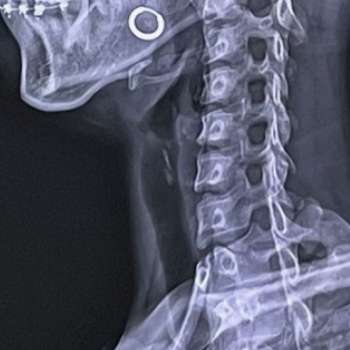

목디스크, 또는 경추 추간판 탈출증(Cervical Disc Herniation)은 목 부위의 디스크가 탈출하거나 돌출되어 신경을 압박하는 상태를 말합니다. 이로 인해 통증, 감각 이상, 근력 저하 등이 발생할 수 있습니다. 목디스크의 원인은 매우 다양하며, 이를 이해하기 위해서는 해부학적, 생리학적, 그리고 생활 습관적인 요인들을 모두 고려해야 합니다. 전문가적 입장에서 목디스크의 주요 원인 10가지를 매우 상세히 설명하겠습니다.